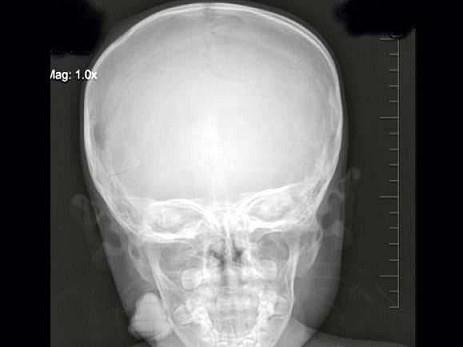

问题 3岁,男,发热伴头顶部局限性疼痛1周,右额顶部可见局限性骨缺损,最可能的诊断是?(?)

选项 A.蛛网膜颗粒压迹 B.先天性颅骨缺损 C.嗜酸性肉芽肿 D.局限性骨皮质缺损 E.以上均不是

答案 C